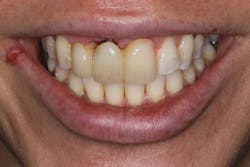

These alveolar bone changes often compromise implant placement due to thin bone volume (figures 2a–2d).

Reduction in quantity and quality of bone can also compromise functional and esthetic outcomes of both implants and fixed bridge restorations (figures 3 and 3a).